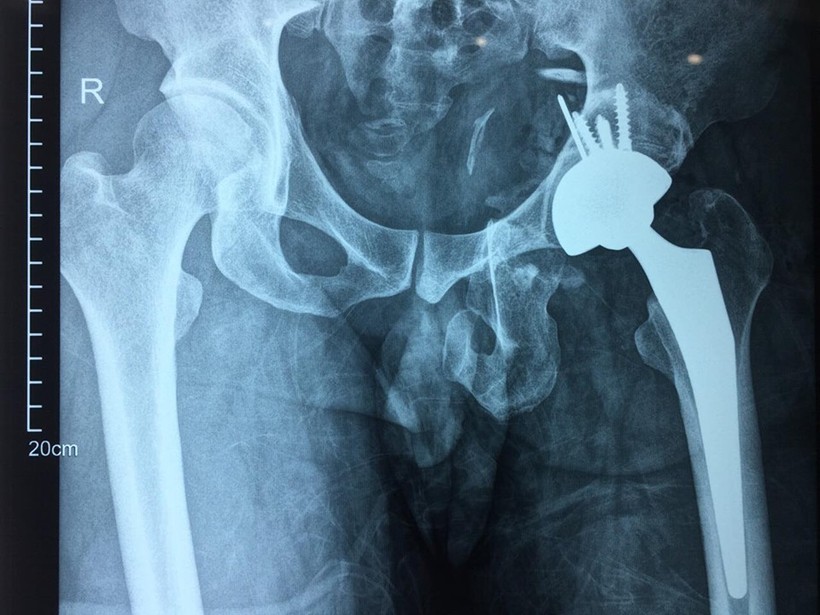

| Phim chụp X-quang của bệnh nhân sau phẫu thuật thay khớp háng. Ảnh: Bệnh viện Hữu nghị Việt Đức |

Đáng chú ý, các bác sĩ đã tiến hành thay khớp háng thế hệ mới - khớp háng không xi măng và 2 chuyển động. Đây là loại khớp đặc biệt có giá trị với bệnh nhân trẻ. Khớp cố định vững chắc giúp biên độ vận động khớp háng rộng, hạn chế mức tối đa nguy cơ bị trật khớp háng, độ mài mòn của khớp ít. Từ đó, tuổi thọ khớp được kéo dài, tối thiểu 30-40 năm. Sau phẫu thuật, người bệnh có thể vận động sớm, phục hồi nhanh.